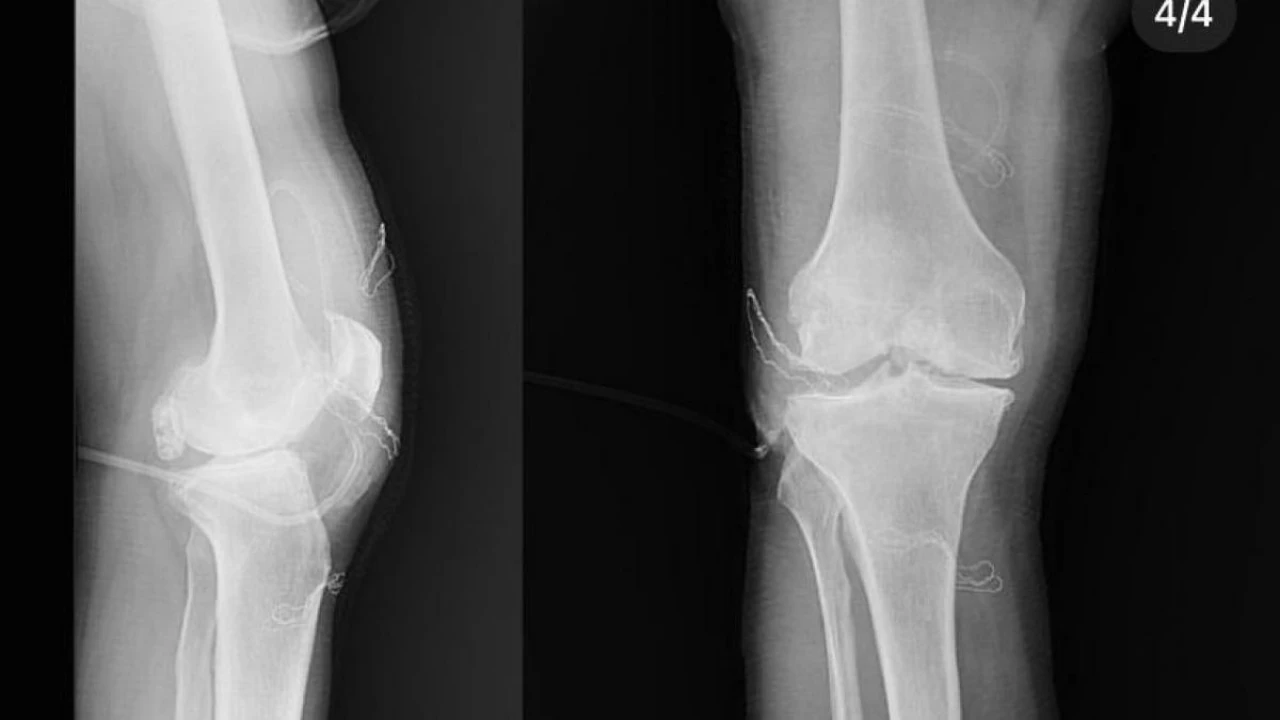

Diz ağrısı şikayeti ile geldiği Düzce Üniversitesi Tıp Fakültesi Hastanesi’nde ameliyata alınan hastanın dizlerinden toplam 41 adet multipl sinovial kondromatozisi çıkartıldı. Özellikle diz eklemi çevresinde görülmekle birlikte kalça, dirsek ve diğer eklemlerde de görülen, ufak parçalardan oluşan cisimler olarak tanımlanan eklem faresi, eklem çevresinde eklem sıvısı ya da sinoviyumda görülen kıkırdak ya da kemik parçalarıdır. Eklem farelerinin boyutları birkaç milimetreden birkaç santimetreye kadar çıkabiliyor.

Düzce Üniversitesi Tıp Fakültesi Hastanesi Ortopedi ve Travmatoloji Kliniği’nde başarılı geçen operasyonu; Doç. Dr. Zekeriya Okan Karaduman, Doç. Dr. Mehmet Arıcan ve Dr. Öğr. Üyesi Sönmez Sağlam gerçekleştirdi.